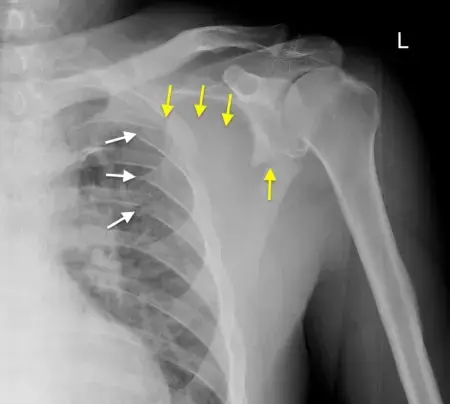

كسور لوح الكتف: تشخيص دقيق، علاج فعال، وتعافٍ أسرع!